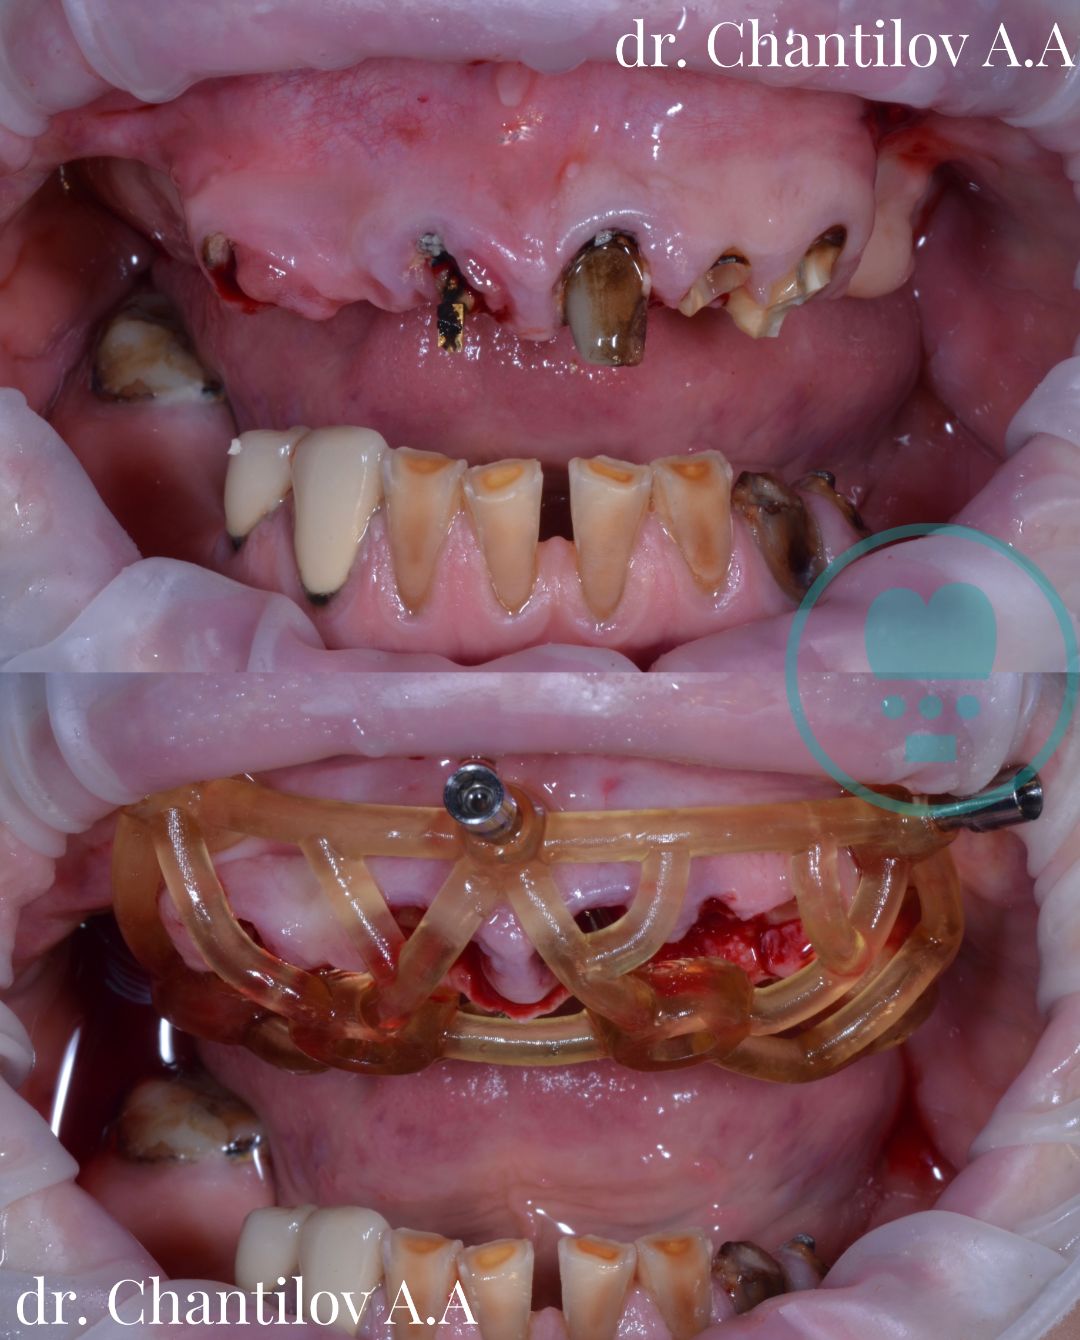

Имплантация зуба

Имплантация зубов челюсти - фото до и после

Изготовление индивидуального шаблона